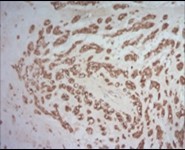

Figure 7.Parachordoma depicting immune reactivity to S100 protein 16.